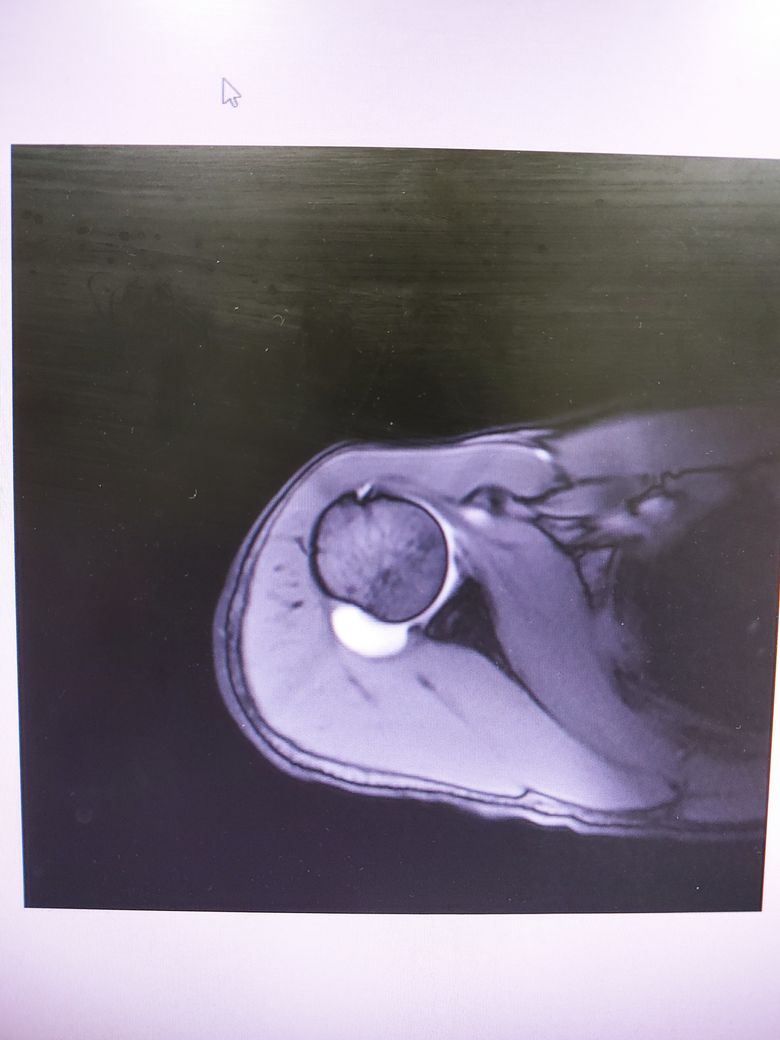

팔이 잡아당겨지는 사고 이후 통증이 지속되어

조영제 투입 후 mri 촬영을 하였습니다.

진단명은 상부관절와순파열(슬랩)이며

헬스와 같은 운동을 계속 하려면 수술이 필요하다 하였습니다.

슬랩이 맞나요? 맞다면 파열 진행 정도는 어느정도인지..

궁금합니다..최대한 사진 많이 올립니다 감사합니다..